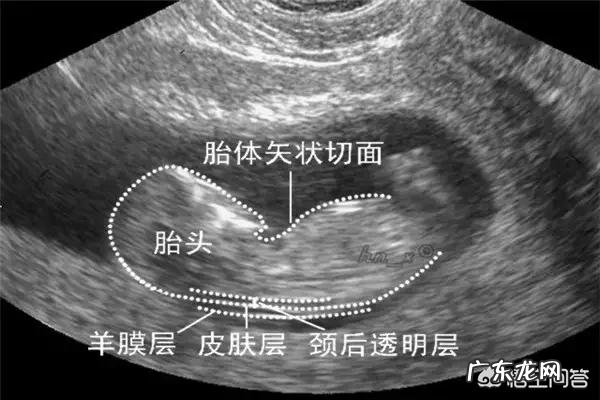

1,早唐筛:11~13+6可以做,主要通过NT+血清指标来判断,检出率85%左右 。